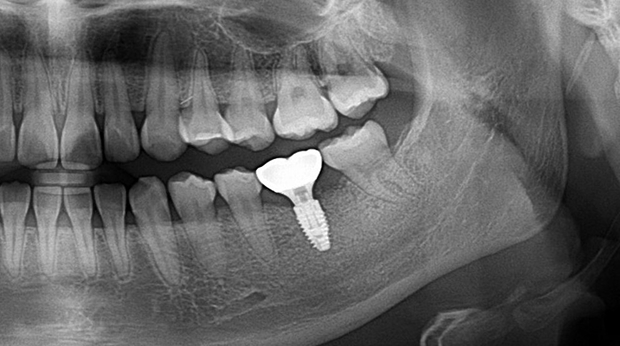

의식하진정법(수면마취)/임플란트

임플란트와 사랑니 발치는 외과적 시술로 잇몸을 절개하는 외과적 시술은

짧으면 짧을 수록 시술 후 붓기와 통증이 최소화됩니다.

치과의사 경력 14년차 구강외과 전문의가 빠르고 안전하게, 아프지 않게 수술해 드립니다.